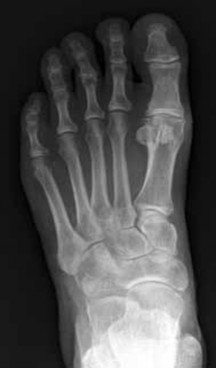

Question 21:

A 32-year-old female presents with a painless, slowly enlarging mass behind her knee. The radiograph is shown. Biopsy confirms a low-grade, bone-forming tumor on the surface of the posterior distal femur with a 'string sign' representing radiolucency between the tumor and the cortex. Which of the following genetic alterations is most classically associated with this diagnosis?

Correct Answer: MDM2 and CDK4 gene amplification

Explanation:

The clinical scenario and imaging description represent parosteal osteosarcoma, a low-grade surface osteosarcoma typically found on the posterior aspect of the distal femur. It is characterized molecularly by ring chromosomes and amplification of the 12q13-15 region, which includes the MDM2 and CDK4 genes. t(11;22) is associated with Ewing sarcoma. t(X;18) is seen in synovial sarcoma. GNAS mutations are found in fibrous dysplasia. EXT1 mutations are associated with hereditary multiple exostoses.